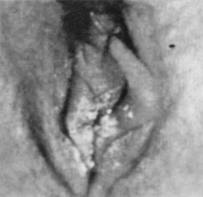

1.4.2.7.3三、临床表现